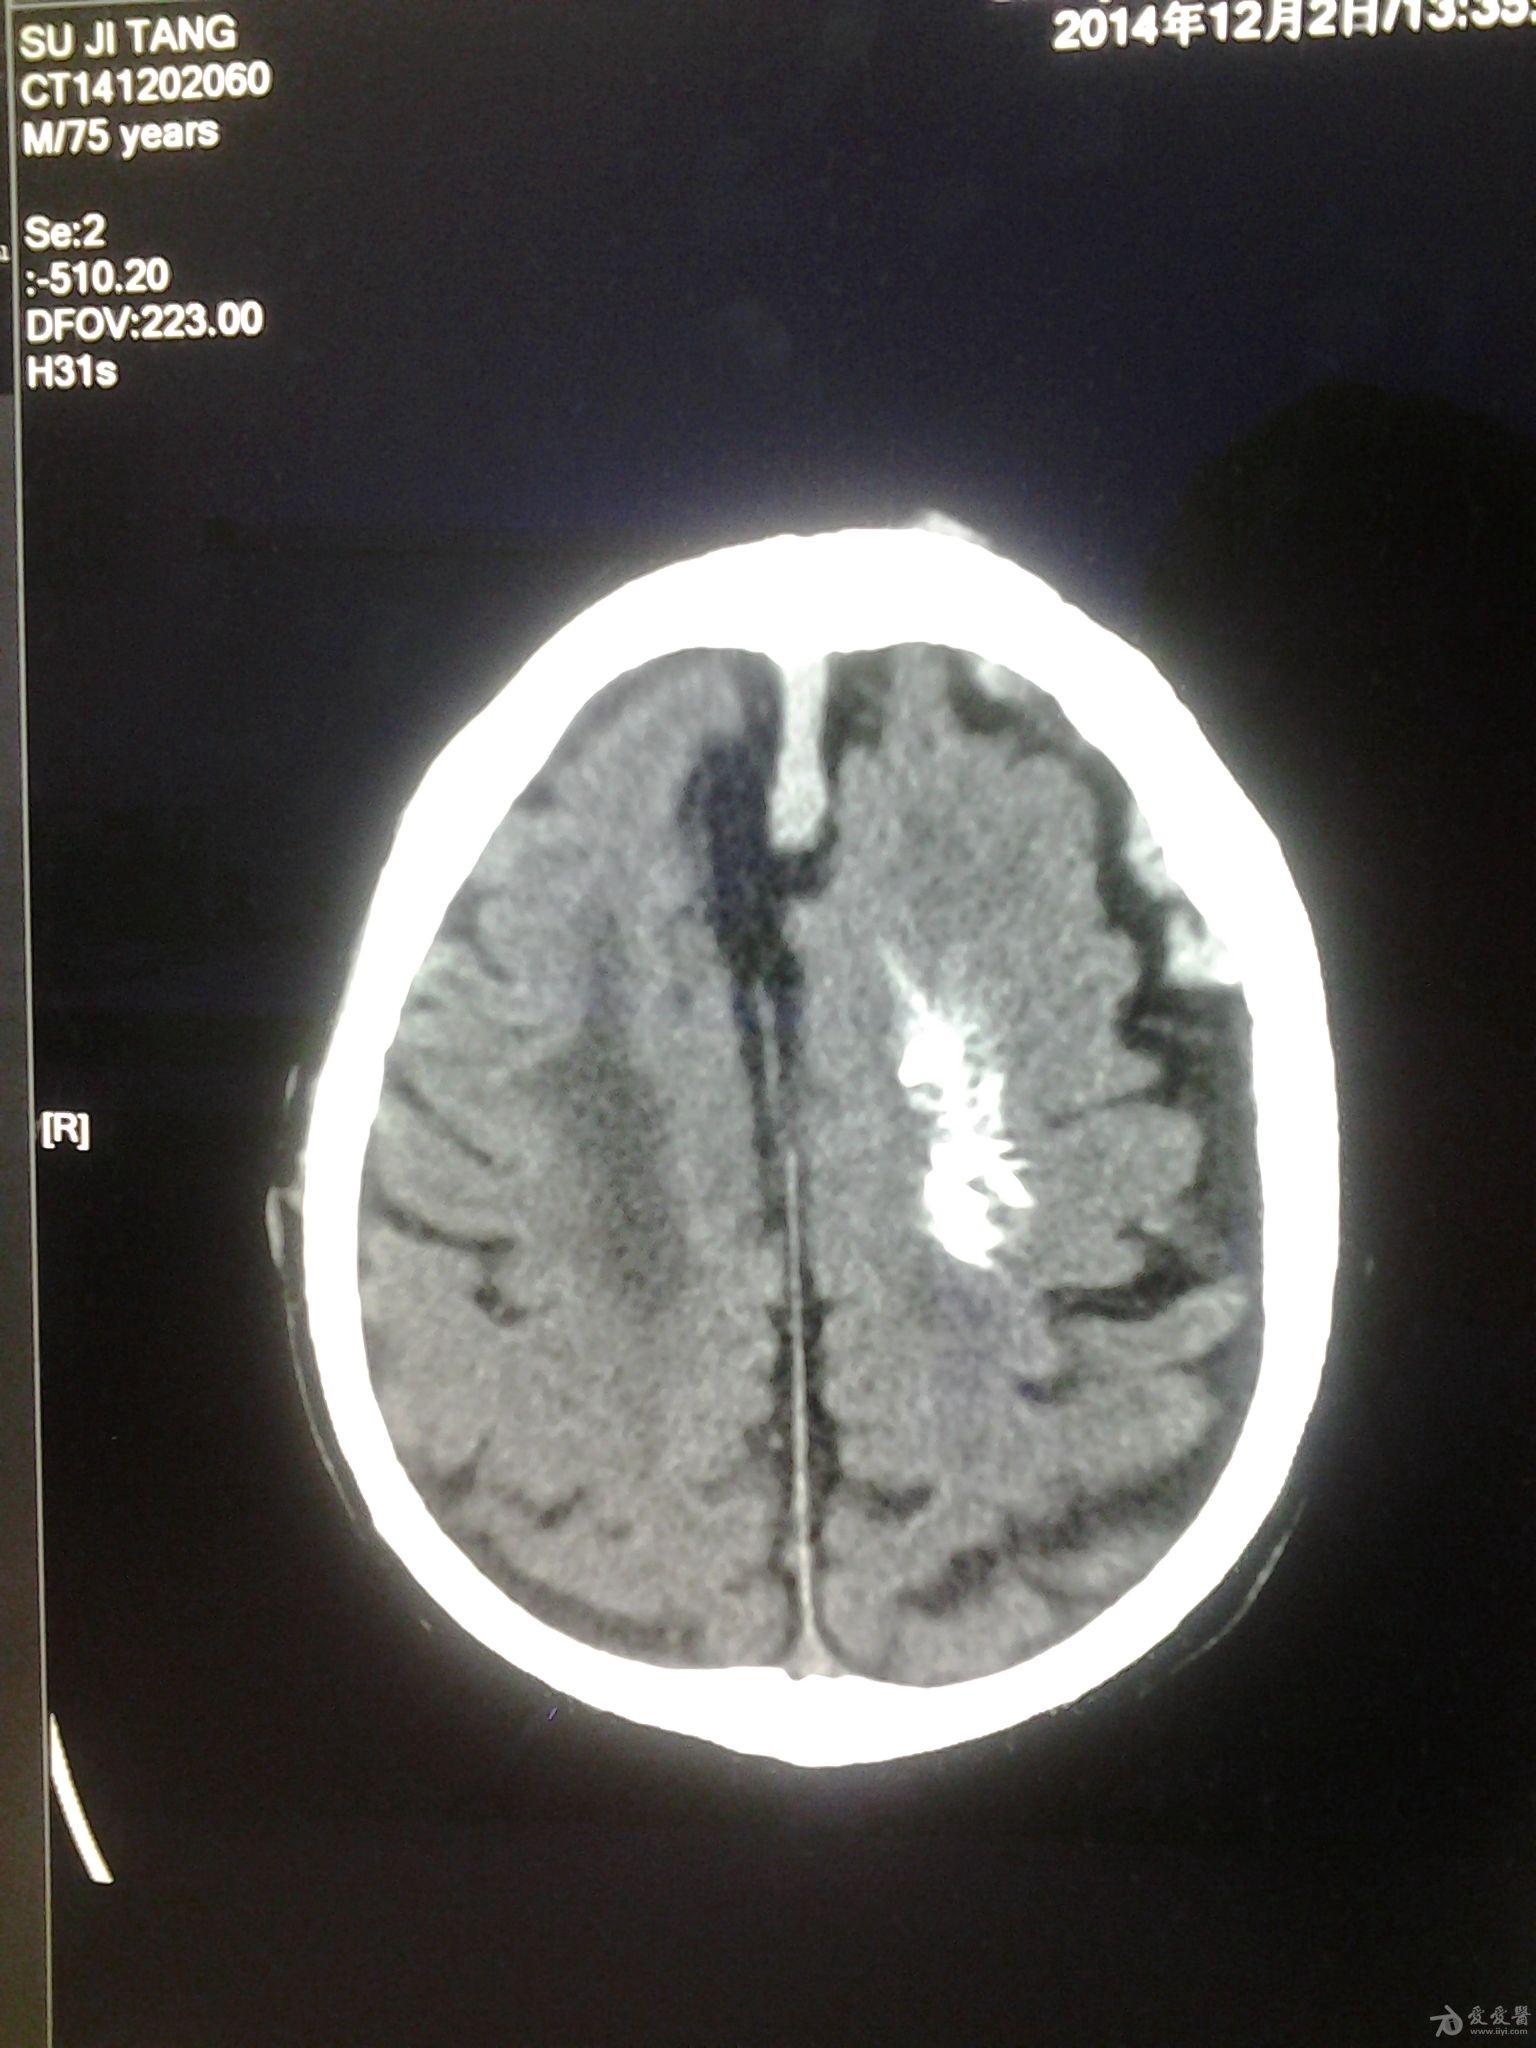

颅内脑血管畸形

图片尺寸1080x1440

右额软脑膜动静脉畸形栓塞术

图片尺寸2659x1816